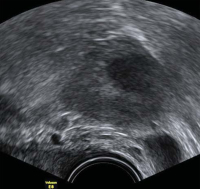

Tipps und Tricks im Gyn-Ultraschall: Sonographische Kennzeichen des Corpus luteum

Journal für Gynäkologische Endokrinologie 2013; 7 (4) (Ausgabe für Österreich): 24-26 Journal für Gynäkologische Endokrinologie 2013; 7 (4) (Ausgabe für Schweiz): 28-30 Volltext (PDF) Abbildungen